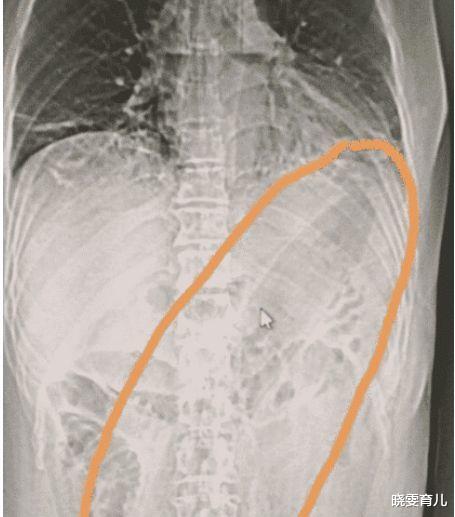

这位女子来自贵州 , 在半夜时分就急匆匆的闯进医院 。 脸色慌张的对着医生表示:“医生快救救我 , 我肚子好痛啊 , 它一溜烟就进去了 , 怎么都拔不出来”!看到女子如此惶恐 , 医生也不敢怠慢 , 于是带她去拍摄了X光 。 看到照片后 , 医生也倒吸了一口凉气 。 因为卡在女子肚子里面的居然是一根长达30厘米大茄子 , 而且都快要顶到心脏位置了 , 情况为此的危急 。